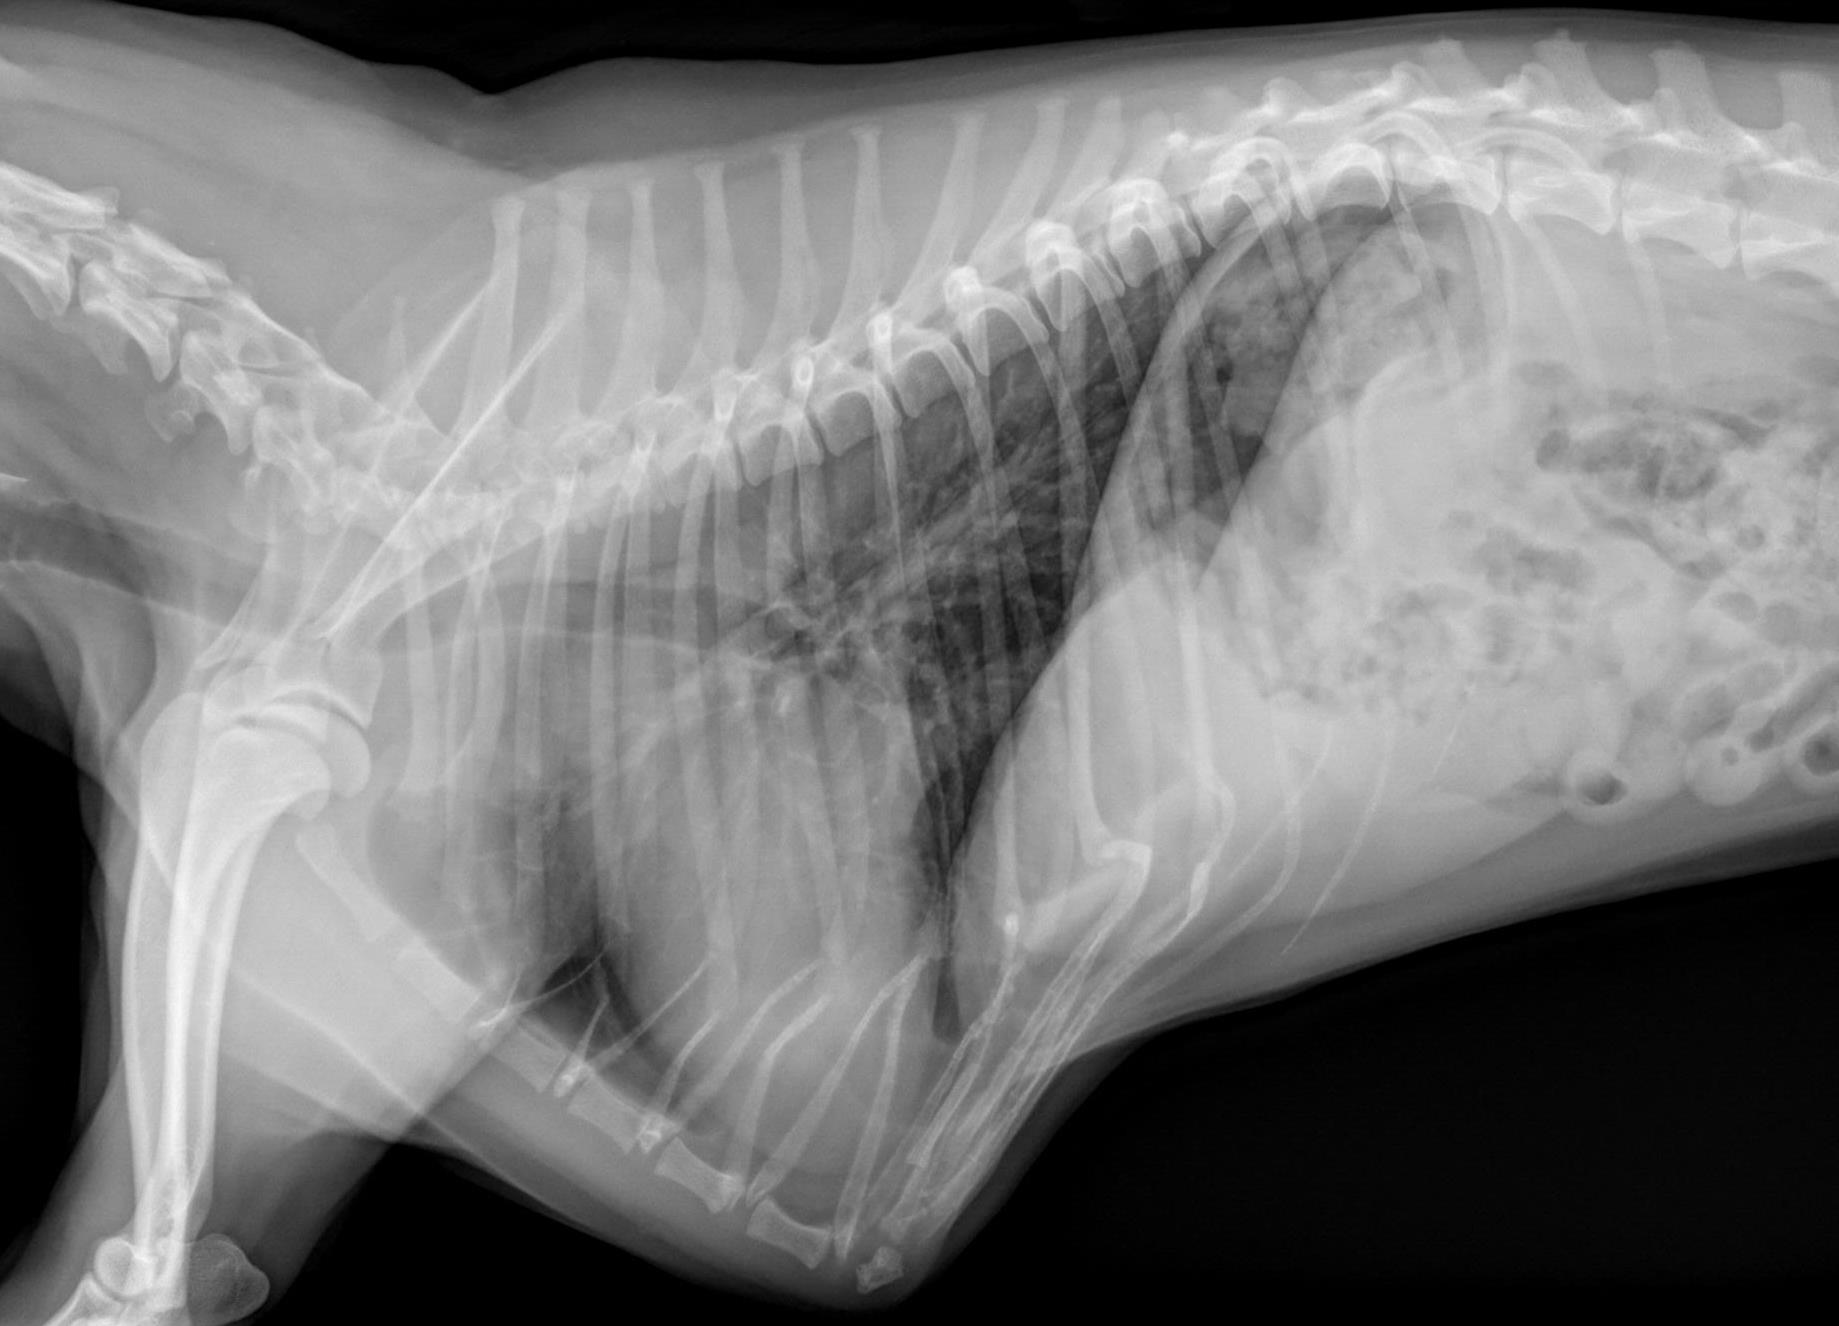

This reminds me of a recent patient with lar par, Sparky, an 11 year old Labrador. He was suffocating and was diagnosed with laryngeal paralysis. This is a serious and stressful condition where the larynx (voice box) doesn’t allow enough oxygen to flow into the lungs.

Prior to surgery, chest X-rays were taken to make sure there was no spreading to the lungs. Blood work was normal, and it was decided that Reese was a good candidate for anesthesia and surgery.